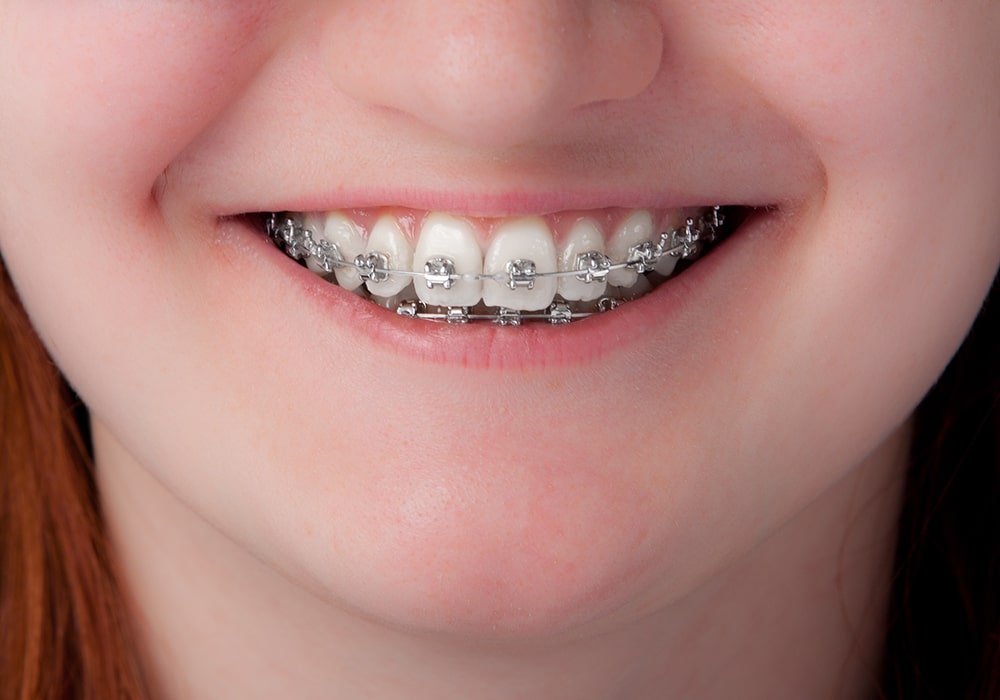

一期治療を終えたお子さまに、必要に応じて行います。二期治療では、一期治療で整えられた顎の上に、歯がきれいに並ぶよう細かな調整をしていきます。永久歯が生え揃ってから、主に成人と同じ矯正治療を行います。

永久歯の歯並びやかみ合わせを確認します。二期治療が必要な場合は、ワイヤー矯正での治療に移行します。